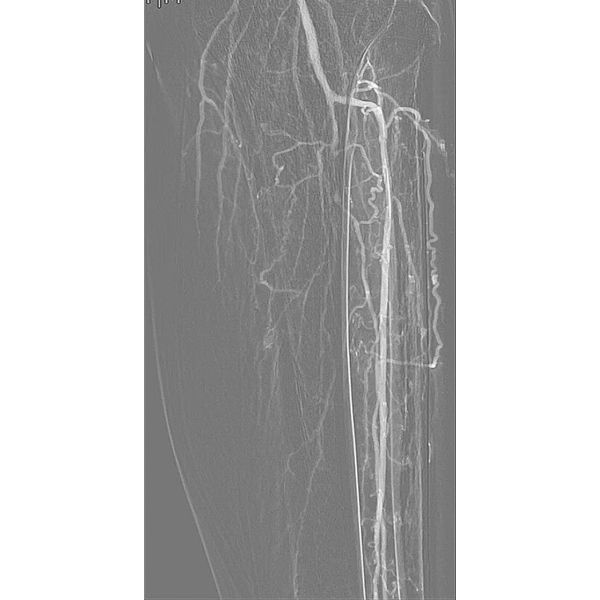

Пациенту провели транслюминальную баллонную ангиопластику магистральных (крупных) артерий левой ноги со стентированием поверхностной бедренной артерии. В ходе операции мужчине в закупоренную артерию ввели баллонный катетер, чтобы расширить её, и установили специальный каркас, который поддерживает просвет сосуда и нормальный кровоток. После этого ему провели некрэктомию — удалили отмершие ткани на стопе.

После внутрисосудистой операции у пациента перестала болеть левая нога. Через пять дней после установки ему сняли вакуумную систему. По всей площади раны образовалась стойкая грануляционная ткань, которая стала основой для последующего формирования эпителия (слоя кожи) и привела к полному заживлению.

Благодаря проведённой операции удалось полностью восстановить адекватное кровообращение в левой ноге, обеспечить заживление язвы и предотвратить ампутацию.